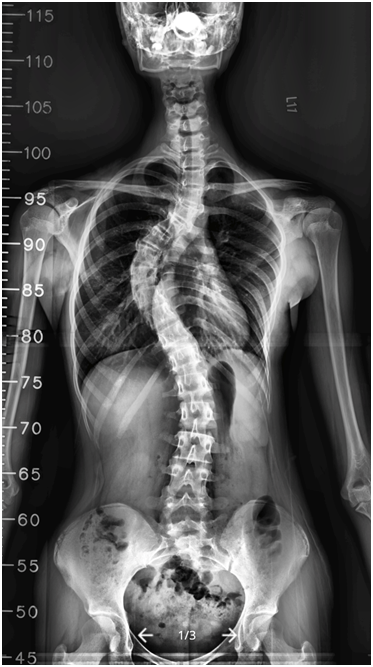

當患者前來求診時,基本的身體視診與檢查做完後就要照X光來計算側彎角度,這關係到以後的治療選擇,尤其在即將進入青春期的小女生是很重要的,因為他們在此時期發育快速,經常幾個月後角度便大幅增加,需要穿背架矯正或甚至要動手術,所以這個階段的追蹤非常重要,不可不慎。治療根據側彎的角度決定。輕度的脊椎側彎可以做脊椎的伸展與柔軟運動並定期門診追蹤;若側彎的角度介於20~40度,就建議穿矯正型背架。醫師會根據側彎發生在胸椎或腰椎而處方不同型態的背架,重點是穿著的時間一定要夠,除了洗澡時取下,整日都要穿著,包含睡覺時間,一直穿到青春期結束,側彎角度不會再有變化為止。若照相側彎角度大於40度時,可能就需要手術治療以防止角度繼續增加造成嚴重胸廓變形,會影響到心臟與呼吸功能及神經壓迫。

術前50度 → 術後10度